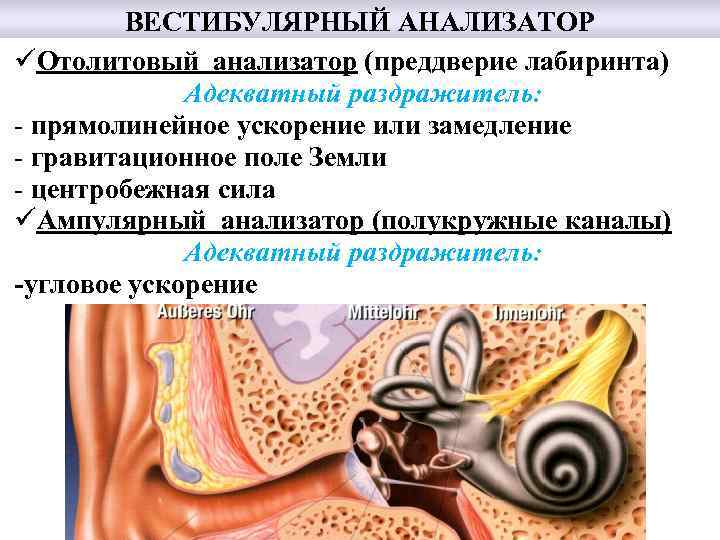

ВЕСТИБУЛЯРНЫЙ АНАЛИЗАТОР üОтолитовый анализатор (преддверие лабиринта) Адекватный раздражитель: - прямолинейное ускорение или замедление - гравитационное поле Земли - центробежная сила üАмпулярный анализатор (полукружные каналы) Адекватный раздражитель: -угловое ускорение